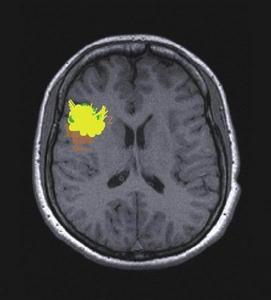

1.CT MRI檢查 腦室系統擴大並尤以側腦室前角為著;側腦室周圍特別是額角部有明顯的間質性水腫帶;腦室擴大的程度甚於腦池的擴大;腦回無萎縮表現 腦溝不加寬。不過,需要與腦萎縮相鑑別,因為嚴重腦挫傷、軸突損傷、腦缺血 缺氧和壞死等造成的腦萎縮也具有腦室擴大的CT影像。後者的特點是:側腦室普遍擴大 腦溝增寬、無腦室周圍的透亮水腫區。MRI檢查雖與CT所見相同,但更為明確和清晰:首先是側腦室前角的擴張及腦室周圍的間質性水腫帶,可於T2加權圖像上顯示出明顯的高信號;其次於冠狀面可以測出兩側室頂之間的夾角小於120°,相反在腦萎縮病人此角則常大於140°;再者於矢狀面尚可看到第三腦室呈球形擴大,視隱窩和漏斗隱窩變淺變鈍,而在腦萎縮病人,其第三腦室前後壁、漏斗隱窩、視隱窩則無明顯變形,雖有擴大但仍保持其原有輪廓。